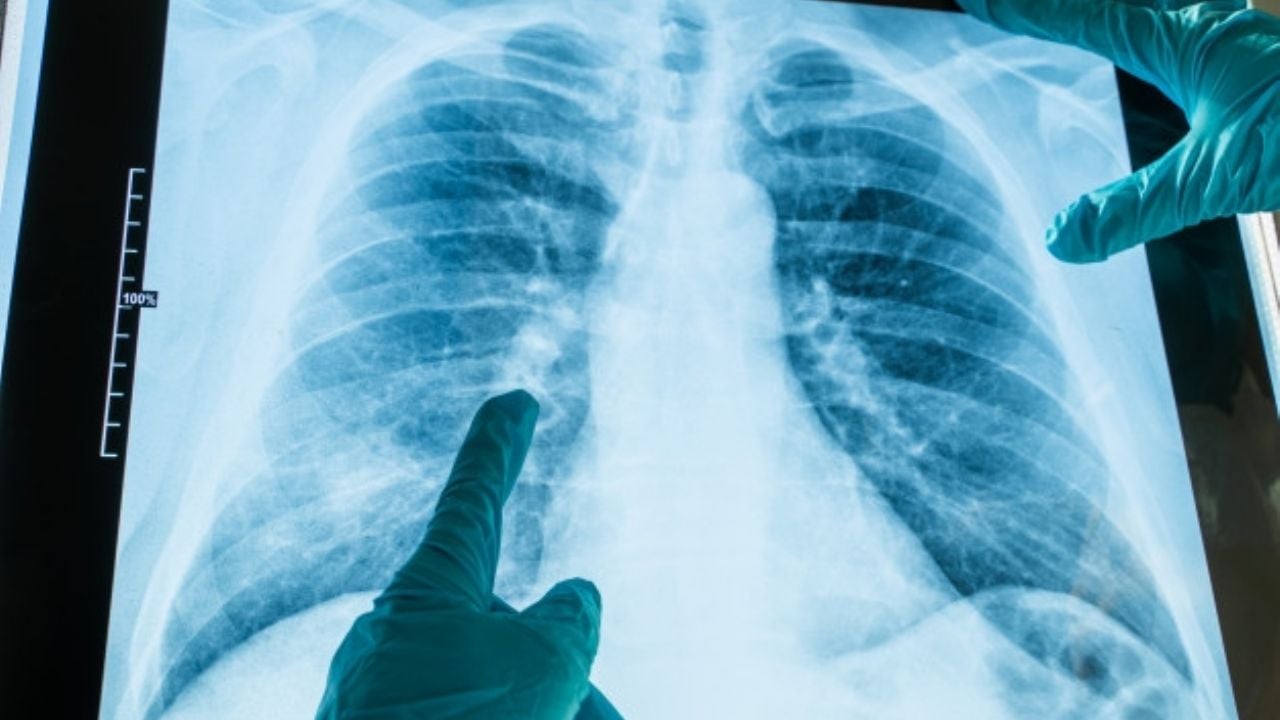

Una investigación realizada por laUniversidad de Washington, ha concluido que estas herramientas innovadoras para detectar elCovid-19con ayuda deradiografías pectoralesno tienen la precisión y eficacia que se espera.

Los expertos asegura que esto se debe a que las pruebas con inteligencia artificial recurren aatajosque da a los médicos resultadosfalsossobre eldiagnósticoy elestado realde laenfermedad, ya que no se basan en lo representado en las imágenes.

Recurren a atajos de aprendizaje que desembocan en asociaciones falsas entre factores médicos irrelevantes y el estatus de la enfermedad . . . los médicos esperarían que un diagnóstico de Covid-19 a partir de una radiografía estuviera basado en pautas específicas dentro de la imagen que reflejarán los procesos de la enfermedad”, explican los investigadores.

Sin embargo, sus conclusiones aseguran que este tipo desistemas automatizadosutilizan factores como laedaddel paciente para determinar si se trata de uncontagio, según los expertos, si este tipo de pruebas detectan que se trata de unadulto mayor, automáticamente lanzan un resultado positivo alvirus, ya que la mayoría de los contagiados son de este sector población.

Los especialistas aseguraron que no es incorrecto asumir que una persona mayor esta infectada, pero son asociaciones inesperadas que pueden llevar a diagnósticos falsos, por lo que recomiendan que este tipo de pruebas no se aplique más quehospitales especializadosen este tipo de inteligencia artificial.